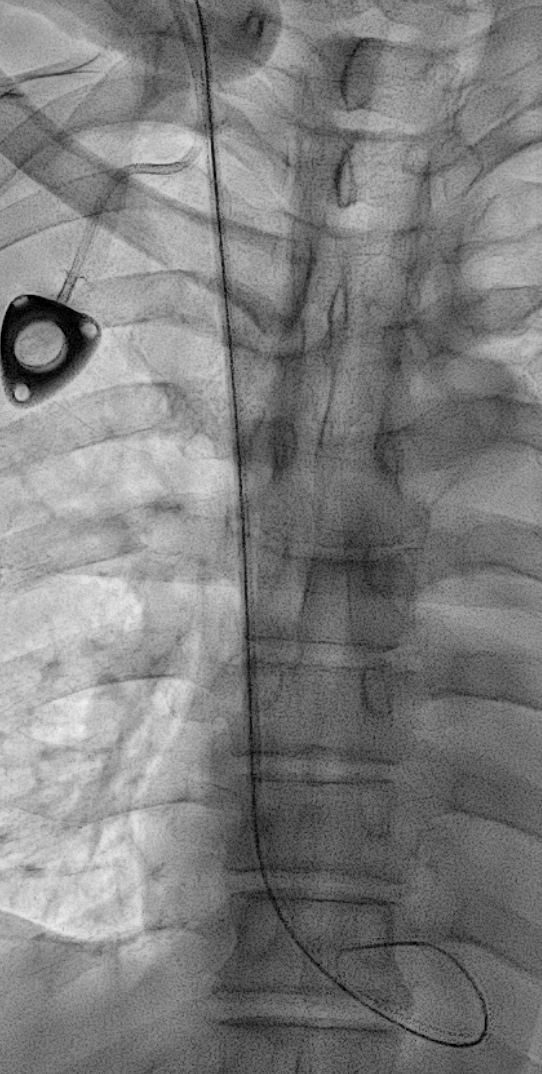

바늘이 들어가고 나면 바늘의 뒷 구멍으로 아주 가느다란 와이어를 삽입합니다. 와이어가 머리카락 처럼 가늘어서 이 와이어를 Hair wire 라고 부릅니다.

X-ray 를 보면서 이 와이어가 적절한 위치로 가는지 잘 봐야합니다.

대부분의 경우는 상대정맥으로 잘 내려가지만 내려가는 경로 상 기정맥(Azygos vein)이나 내흉정맥(Internal thoracic vein)이 있을 수도 있거든요.

이런 정맥들로 잘못 들어가게 되면 정맥포트가 금방 기능을 잃어버립니다.